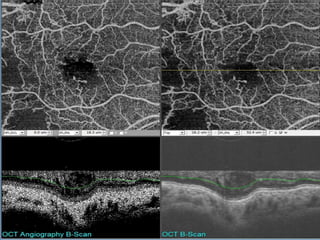

El documento resume los nuevos avances en angiografía de dominio óptico de coerencia tomográfico (OCT-Angiografía), una técnica no invasiva que permite visualizar la microcirculación retinal sin usar contraste. Explica que usa técnicas avanzadas de procesamiento de imágenes para aislar la microcirculación a partir de imágenes de OCT mediante el análisis de decorrelación. Finalmente, destaca algunas de sus aplicaciones clínicas actuales como la evaluación de neovasos en degeneración macular y retinop